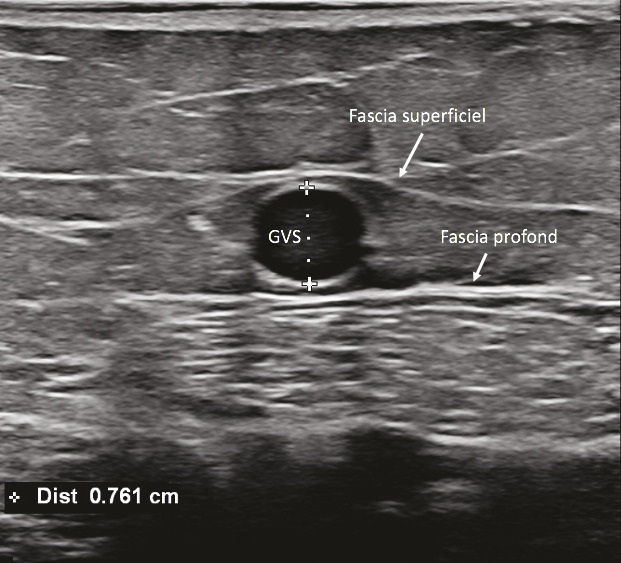

L’échographie en mode B, qui fournit une simple imagerie tissulaire, est utilisée pour identifier le réseau veineux superficiel, analyser les trajets veineux, mesurer le diamètre des veines pathologiques et analyser leur paroi et leur système valvulaire (fig. 12 et 13).